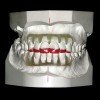

Figure 11  Orthodontics are required to intrude the mandibular anteriors and create space for their build-up.

Figure 11

Figure 12  Orthodontics are required to intrude the mandibular anteriors and create space for their build-up.

Figure 12

Again, the starting point is a set of mounted models, an orthodontic set-up, and a diagnostic wax-up. The worn teeth are cut from the set-up and waxed to normal length. They are then replaced in the set-up and become the guide for treatment. Whether they are lengthened before or during orthodontics depends upon whether space exists to lengthen them prior to orthodontics. If it does, they can be temporarily restored prior to treatment. If not, the orthodontist must first create space, then de-bracket the worn teeth and send the patient to the restorative dentist for temporary restoration. The brackets are then replaced and the orthodontics completed. The need to open space prior to correcting tooth length is common when utilizing orthodontics to intrude severely worn and over-erupted maxillary or mandibular incisors (Figure 2, Figure 3, Figure 4 and Figure 5).